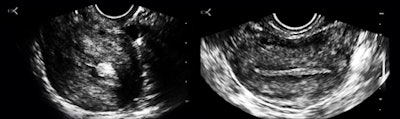

A 64-year-old man was being readied for transfer to an emergency room because the intake identified him as having chest pain. I noticed that he was sitting upright without any obvious distress, breathing slowly, and without diaphoresis or agitation. On inquiry, I was told that his heart rate was 72, his blood pressure was normal, and the automated analysis of the electrocardiogram was "normal." I asked to see him while the transfer was being arranged.

The patient was agreeable and very cooperative. He unbuttoned his shirt, and I did a quick cardiac survey: There was normal LV wall thickness; no asymmetrical septal hypertrophy; normal chamber proportions; great looking mitral, tricuspid, and aortic valves; and, most significantly, no regional LV wall movement abnormality. There was no pleural or pericardial effusion or dilatation of hepatic veins. He denied chest pain or dysphagia.

Figure 6: Apical four-chamber and mitral-valve views.I was thinking about the reflectors around the crux of the heart and how much of the apparent atrial volume disparity was a scan-plane effect when I continued looking and came upon something of more immediate concern (figure 7).